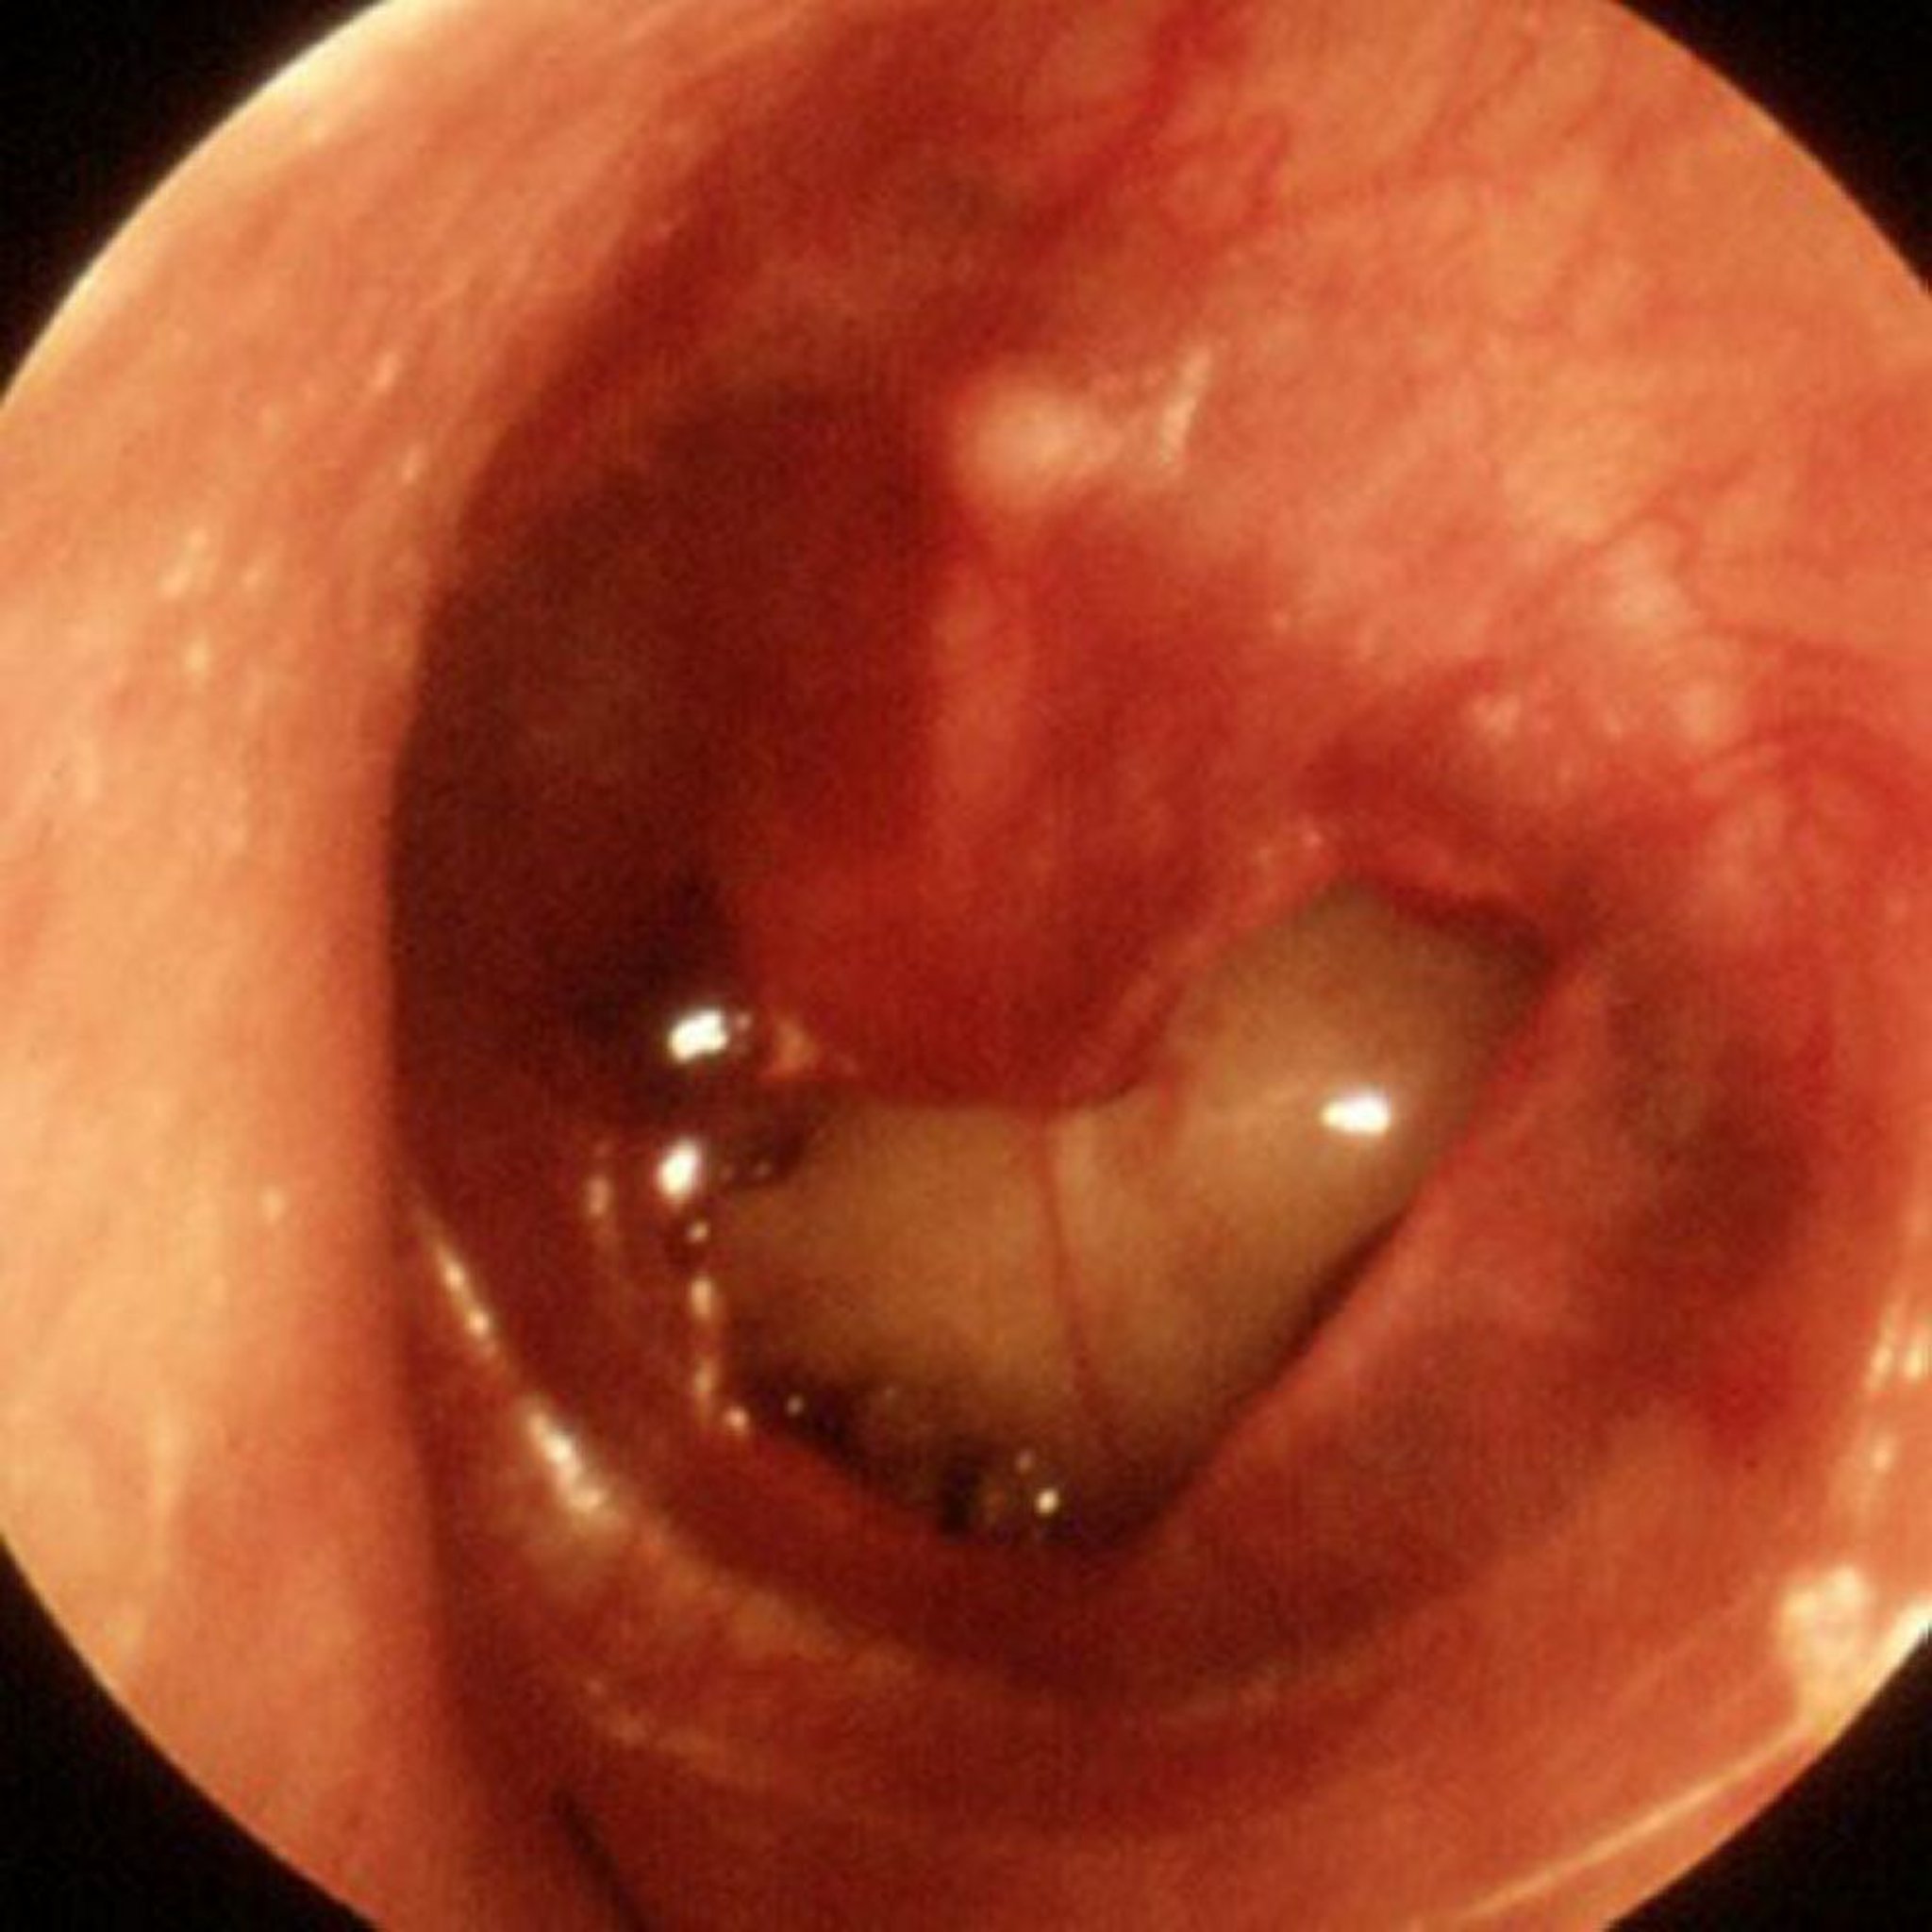

Травматична перфорація барабанної перетинки

A large traumatic perforation is seen in this image.

Image provided by Piet van Hasselt, MD.